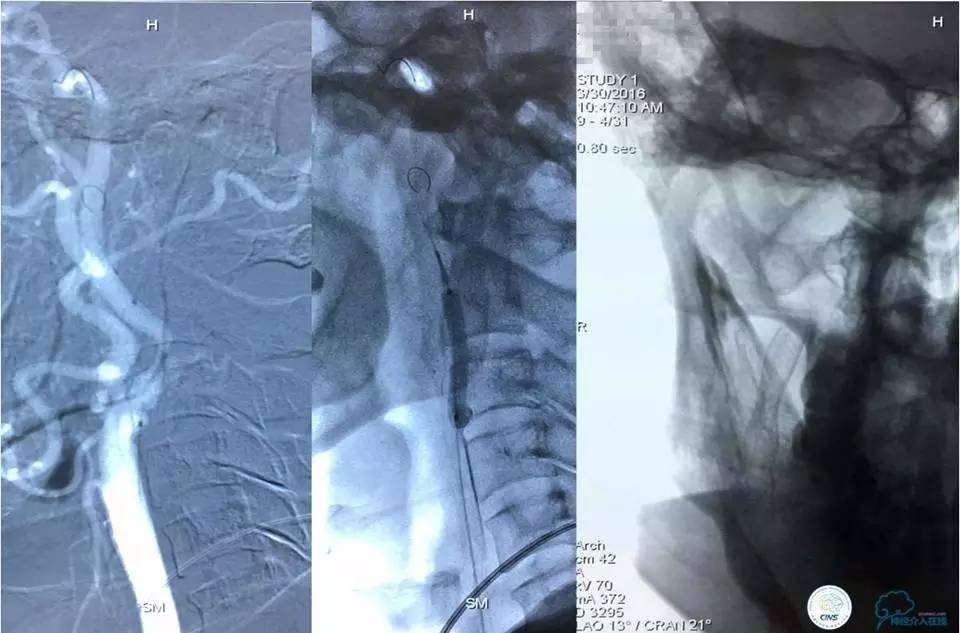

手术经过如下:

路径图下沿导引导管送入TRANSEND微导丝(0.014″长度300cm)小心通过狭窄段至左侧大脑后动脉P3段,沿微导丝送入Gateway球囊(2mm×22mm)至狭窄段,准确定位后球囊逐渐加压至7atm,可见球囊完全张开,快速抽瘪球囊,造影显示狭窄段较前明显改善,残余狭窄率约70%,考虑到球囊扩张后仍有较高残余狭窄,为防止弹性回缩导致再狭窄及血栓形成,尽快行支架置入术。

撤出球囊,沿微导丝送入ENTERPTISE (4.5mm×22mm)自膨式支架至狭窄段,准确对位后成功释放支架,造影显示双椎动脉颅内段及基底动脉前向血流好,支架贴壁良好,动脉夹层消失,残余狭窄约30%。支架释放完成后,微导管经支架网眼导入瘤腔内,送入弹簧圈数枚并解脱。手术结果如下: